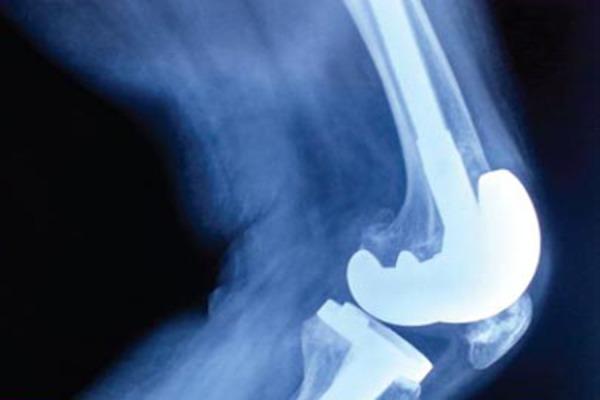

We report an osteoarthritic patient with huge sub-chondral cyst-like lesions in the Anterior part of distal femur. Deep and large bone defects and severe lateral laxity due to Advanced osteoarthritis was successfully treated with semi-constrained type total knee arthroplasty with long stem.

A 70yrs old Female was admitted in our institution diagnosed with severe bilateral Osteoarthritis. The x-rays showed bone on bone Tricompartment OA Knee with Varus Malalignment. She was posted for Single Stage Bilateral Total Knee Replacement and as planned the Left Knee Was Operated first. After exposure, Proximal Tibial, Distal Femoral Cuts and measurement of extension gaps the synovium from the anterior Femur was removed and sizing was done. The AP cut was then proceeded with. We spotted a small Osteochondral Cyst in the Anterior Femur which was curretted to remove the cystic material, which is when we realised that the cyst was large and communicating with the medulary canal. The remaining Femoral preparations was done keeping in mind the risk of iatrogenic fracture and extension Stem was used in the femur. The defect was then packed cancellous bone graft.

我们报告一例患有股骨远端前部巨大软骨下囊肿样病变的骨关节炎患者。因晚期骨关节炎导致的深部和大面积骨缺损以及严重的外侧松弛,采用带长柄的半限制性全膝关节置换术成功治疗。

一名70岁女性因双侧严重骨关节炎入住我院。X线显示三关节骨对骨的膝关节骨关节炎伴内翻畸形。她计划接受一期双侧全膝关节置换术,按计划先对左膝进行手术。暴露后,进行胫骨近端、股骨远端截骨并测量伸直间隙,切除股骨前部的滑膜并进行尺寸测量。然后进行前后位截骨。我们在股骨前部发现一个小的骨软骨囊肿,将其刮除以去除囊肿内容物,此时我们意识到囊肿很大且与髓腔相通。在考虑到医源性骨折风险的情况下完成剩余的股骨准备工作,并在股骨中使用延长柄。然后用松质骨移植填充缺损。